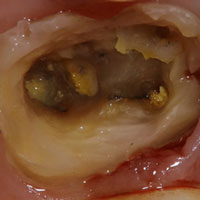

むし歯の進行や外傷、咬み合わせの問題で必要になる歯の根の治療。ときには激しい痛みを伴い、いても立ってもいられないほど苦しむ方もおられる歯の根の病気。

これは、歯の根に膿がたまり、炎症を起こしていることが原因で起こる痛みです。この症状を緩和するには、歯の神経を取り、歯の根にたまった膿を抜き、根管を清潔にしてお薬を入れることで治まります。